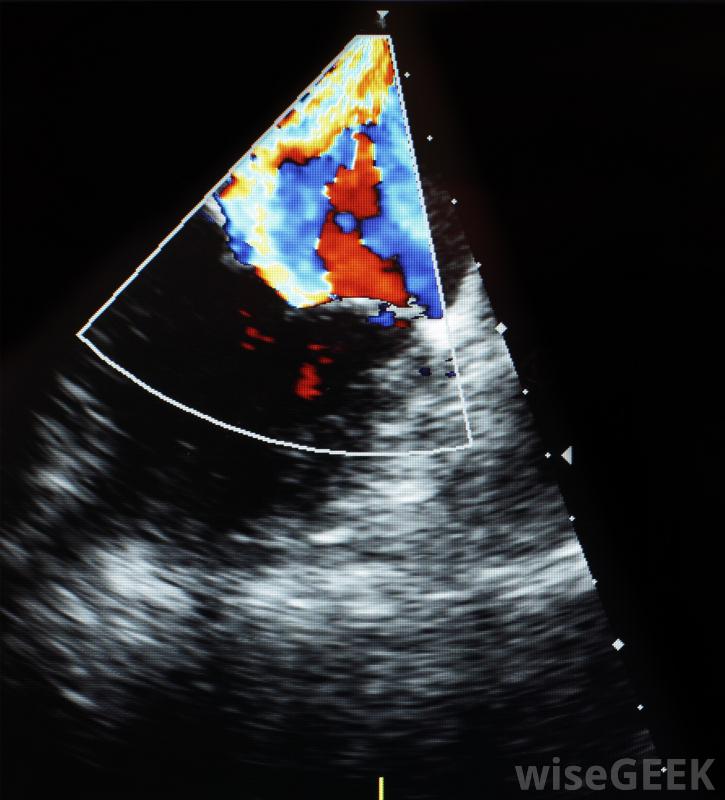

超声心动图是一种诊断测试,它使用声波来产生心脏的图像。它可以用来确定你的心脏是否在泵血,以及是否存在任何结构异常。这些图像可以用来检测你的心肌和瓣膜的不同类型的问题。你的结果应该列出几个一些信息,包括你的心脏大小,泵血强度,以及在测试过程中发现的任何异常。

超声心动图结果将提供有关心脏泵送强度的信息。该测试可以查看特定的测量值,例如每次心跳时从充满的心室中泵出的血液量,或者一分钟内泵入心脏的血液量。测量结果被列为射血分数,或EF。正常EF结果在55%到65%之间。低于45%的数值表明泵送强度有所下降,而低于30%的数字则表明心脏功能明显下降。当心脏无法泵出足够的血液来满足身体需要时,可能会发生心力衰竭。

超声心动图使用高频声波传输到心脏检测心脏的形状、大小和运动。